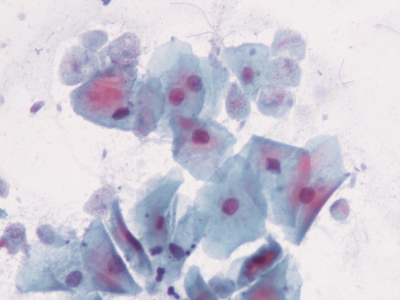

Полово предаваните болести се наричат още венерически болести - на името на богинята на любовта Венера. Това са инфекциозни заболявания, които се предават при сексуален контакт от човек на човек. Те се причиняват от различни микроорганизми - бактерии, вируси, гъби, протозои, паразити. Въпреки че основният път на предаване на инфекцията е вагинален, орален или анален секс, полово предавани болести могат да се разпространяват и чрез кръв или кръвни продукти. Много от тези инфекции - включително сифилис, хепатит В, ХИВ, хламидия, гонорея, херпес и HPV - също така могат да се предават от майка на дете по време на бременност и раждане.

Известно е, че повече от 30 различни микроорганизми се предават чрез сексуален контакт. Осем от тези патогени са свързани с най-голямата честота на полово предавани болести. От тези 8 инфекции 4 в момента са лечими: сифилис, гонорея, хламидия и трихомониаза. Останалите 4 са вирусни инфекции, които са нелечими: хепатит В, вирус на херпес симплекс, HIV и човешки папиломен вирус (HPV). Те се характеризират с хронично протичане и дълго вирусоотделяне и вирусоносителство. Симптомите или заболяването поради неизлечимите вирусни инфекции могат да бъдат намалени или модифицирани чрез лечение.